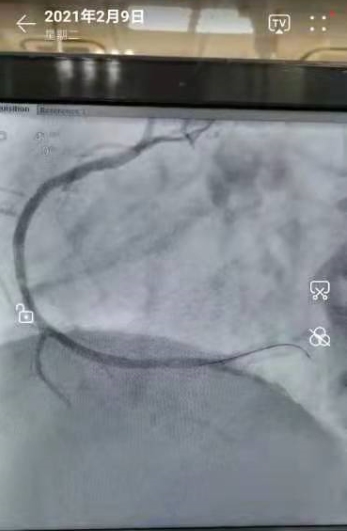

2021年2月9日,心血管内三科的医生们,在导管室正常做着介入手术!今天共3个患者。最后一台是一个胸痛的病人,造影:右冠闭塞99%。与家属沟通后,我们积极地做了开通血管的介入手术。

导丝通过顺利——球囊扩张到位——安放支架成功!

手术完美!